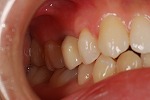

~術前~

歯周治療写真

~術後~